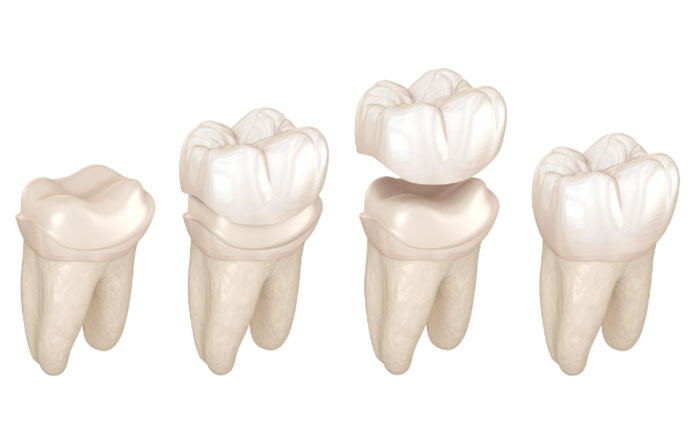

被せ物をつける際に重要になるのがフェルールという概念です。患者さんからすると、聞き馴染みのない難しい言葉かと思います。

フェルールをわかりやすく言うと、被せ物をしっかり固定するための、いわば「のりしろ」のことです。封筒にフタをのり付けするとき、のりしろが広いほどしっかりくっつきますよね。

歯も同じで、歯茎より上に健康な歯が1.5〜2mm以上、周りに残っていないと、被せ物をしっかり固定できません。のりしろが足りなければ、被せ物は食事のたびにグラつき、やがて外れたり、歯ごと割れたりしてしまいます。

歯を引き出すことで十分な高さが確保できれば、先述のフェルールと生物学的幅径を確保できるようになり、被せ物の長期安定も望めるようになります。